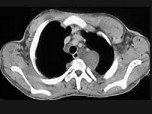

- 单项选择题男,35岁, 皮肤可见咖啡色素斑,关节疼痛, 结合图像,最可能的诊断是 ( )

A、骨肉瘤

B、骨转移瘤

C、神经纤维瘤

D、骨软骨瘤

E、纤维肉瘤